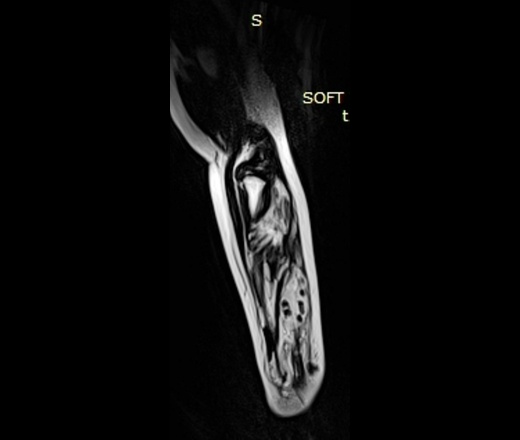

При контролях в динамике - мягкотканный компонент с наличием округлых теней.

УЗИ - мягкотканный компонент с наличием кровотока.

МРТ - гемангиома мягких тканей.

Округлые плотные тени - флеболиты.